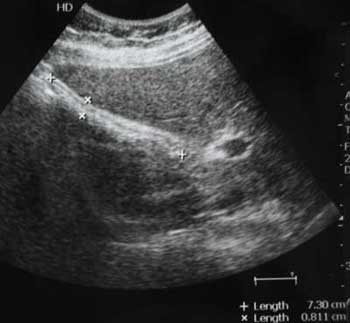

Молодой мужчина с болями в эпигастральной области.

Осматривался дважды натощак. Выявлены изменения желчного пузыря.

Печень, селезенка при УЗИ не изменены.

Думаю,что это не просто пустой ж.пузырь,он содержит гиперэхогенное включение в середине,повторяющее форму ж.пузыря и дающее позадиакустическую тень.Возможна кальцифицированная аскарида

Нефункционирующий желчный пузырь содержит гиперэхогенное включение.

Первый ж.пузырь удален, клинический диагноз "сморщенный желчный пузырь, ЖКБ", гистология - фиброз стенок желчного пузыря.